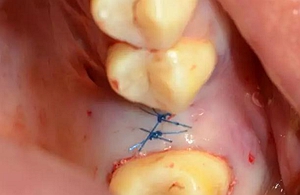

縫合